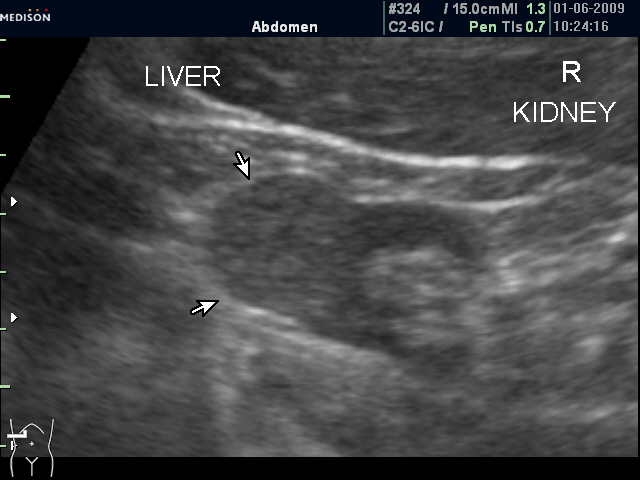

Женщина 72 лет. При УЗИ выявлены два аваскулярные образования: в нижнем полюсе правой почки и у верхнего полюса почки.

Уникальность случая в том, что эти изменения - БЕЗ ДИНАМИКИ с 2005 года.

Опухоль почки?

Опухоль почки и надпочечника.

Без допплера явно опухоль почки